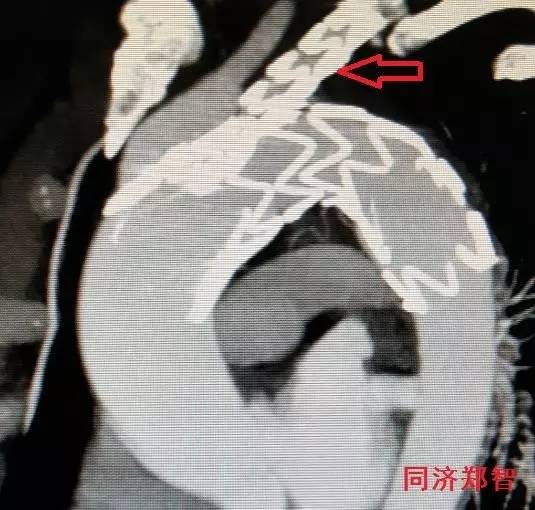

CTA三维重建,红箭头显示胸降主动脉穿透性溃疡合并壁间血肿(图7)。

图7